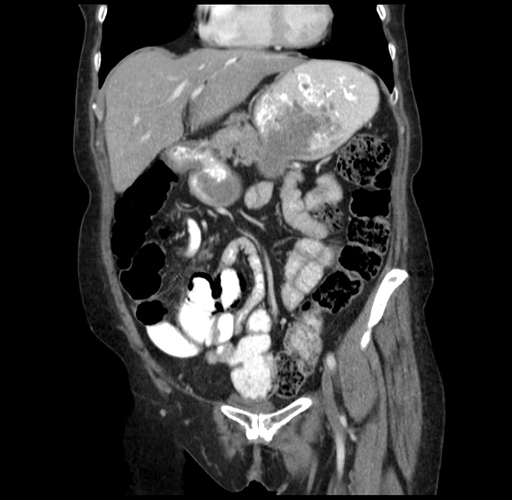

Pre-Chemo: Coronal Venous

Coronal Venous